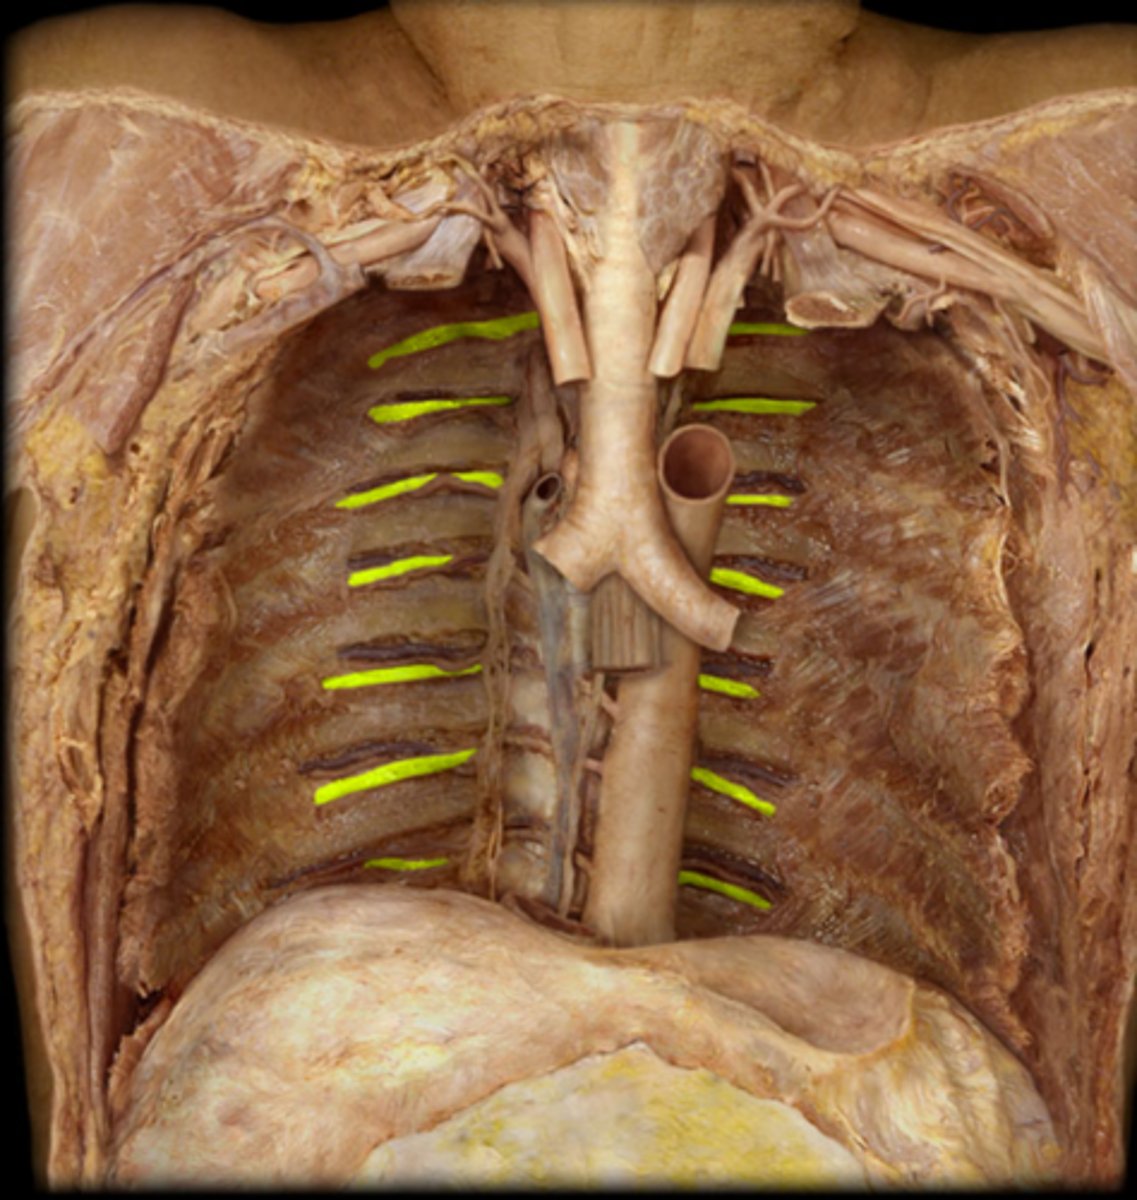

posterior intercostal arteries and veins

intercostal nerves

sympathetic trunk and chain ganglia